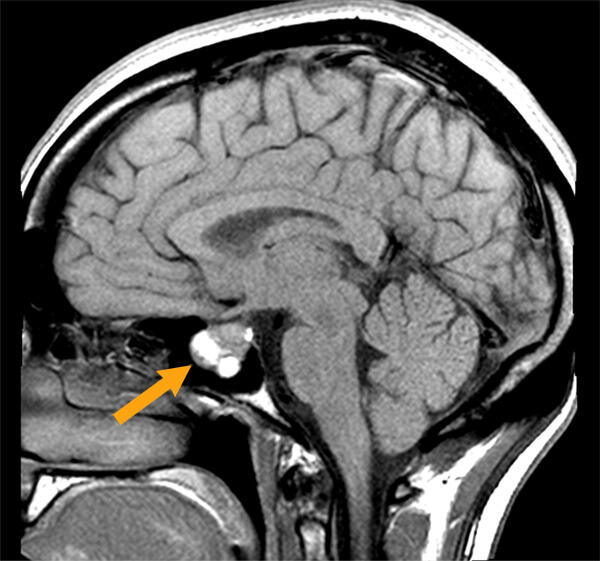

122. The Tumour

Unfortunately, the MRI scans of my tumour have been lost. But this gives you a pretty good idea. Image courtest of Mayfield Clinic

A better sense of where the pituitary gland is located